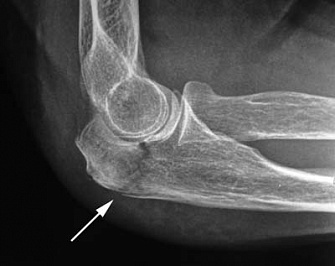

Запитання 20

НА ЯКИЙ СУГЛОБ ВКАЗУЄ СТРІЛКА НА РЕНТГЕНОГРАМІ? КІСТКИ ЯКОГО ВІДДІЛУ СКЕЛЕТУ ВІН З'ЄДНУЄ?

варіанти відповідей

ГРУДНИННО-КЛЮЧИЧНИЙ С.

ПЛЕЧОВИЙ С.

НАДПЛЕЧОВО-КЛЮЧИЧНИЙ С.

АКРОМІАЛЬНО-КЛЮЧИЧНИЙ С.

КІСТКИ ВЕРХНЬОЇ КІНЦІВКИ

КІСТКИ ТУЛУБА І ВЕРХНЬОЇ КІНЦІВКИ